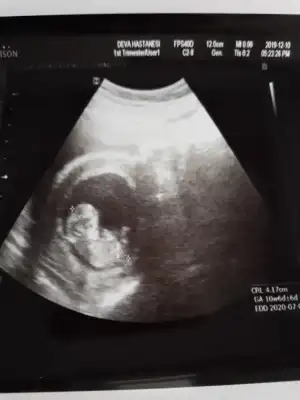

Değişmeyebilir saglıkla gelsinUsg 12 haftalık, doktorun tahmini 16 haftalık![]()

12+1 canım:) doktor da erkek dedi bakalım net değil ama netleşince oy vercemNet olmamakla birlikte erkek diyorum kaç haftalık 11+ yada 12+ olmalı